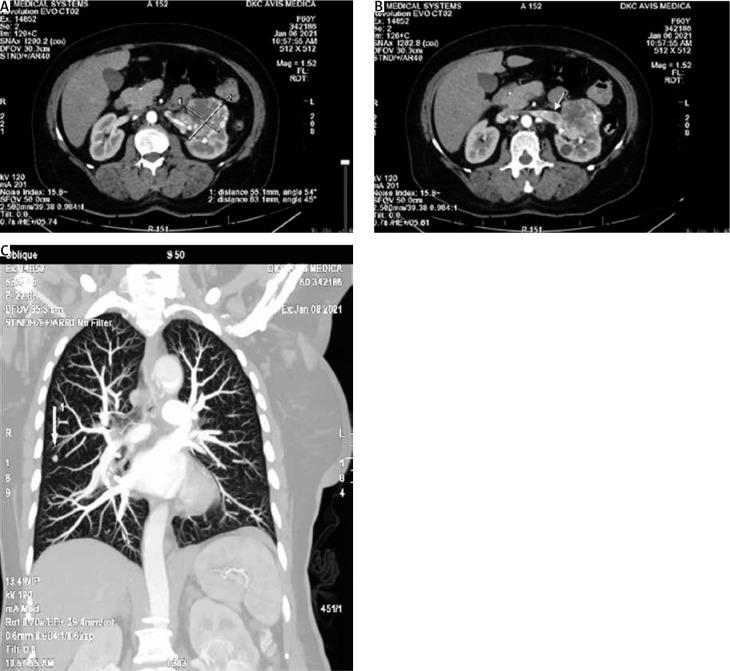

CASE REPORT

We present a case of a 60-year-old patient, in whom the renal cell carcinoma manifested for the first time as an intense bleeding, soft tumour formation with dimensions 4/6 cm originating in the vagina.

我们报告一例60岁患者,其肾细胞癌首次表现为阴道内出现大量出血、大小为4/6厘米的柔软肿瘤形成。